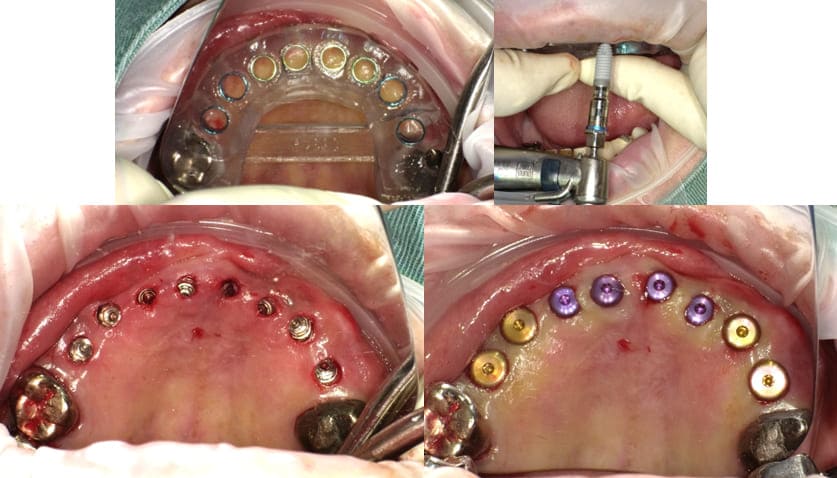

他の温存不可能な残根も抜歯して上顎にインプラント5本を埋入した。なお#16に関してはソケットリフトを併用した。

-

- 治療時の画像(出血などの症例画像あり)

上顎のインプラント埋入後約1か月で、下顎臼歯部#35,36,44,45,46にインプラント埋入を行った。

上顎インプラント埋入手術後4ヶ月でインプラント体と骨の結合を確認して両側上下顎臼歯部のインプラントに上部構造(歯の部分)を装着した。

臼歯部のVertical Stopを確保した上で上顎前歯部のインプラント埋入手術を行った。